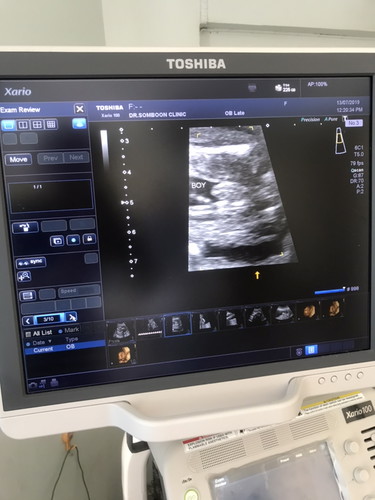

ช่วยดูหน่อยค่ะที่ยื่นออกมานั้นคือจู๋ใช่มั้ยคะ 20 วีคค่ะ หมอบอกผู้ชาย แต่คนแรกก็ผู้ชาย ลักษณะไม่เหมือนของคนแรกค่ะเลยไม่แน่ใจ

ดูจากภาพซาวน์ดูไม่ออกเลยค่ะ แต่ผลซาวน์ boy คือผู้ชายค่ะแม่